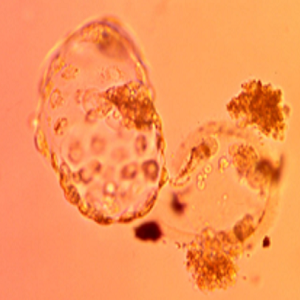

A hatching human blastocyst that developed in SYNBIOS® SYNTHETIC EMBRYO CULTURE MEDIUM. Image was captured using the embryoscope. The hatching occurred naturally. The workers noted that the performance of the SYNBIOS® SYNTHETIC EMBRYO CULTURE MEDIUM was comparable to contemporary conventional protein-containing medium.

Courtesy: Yousef AlHelou, April 2020, Fakih IVF, United Arab Emirates.